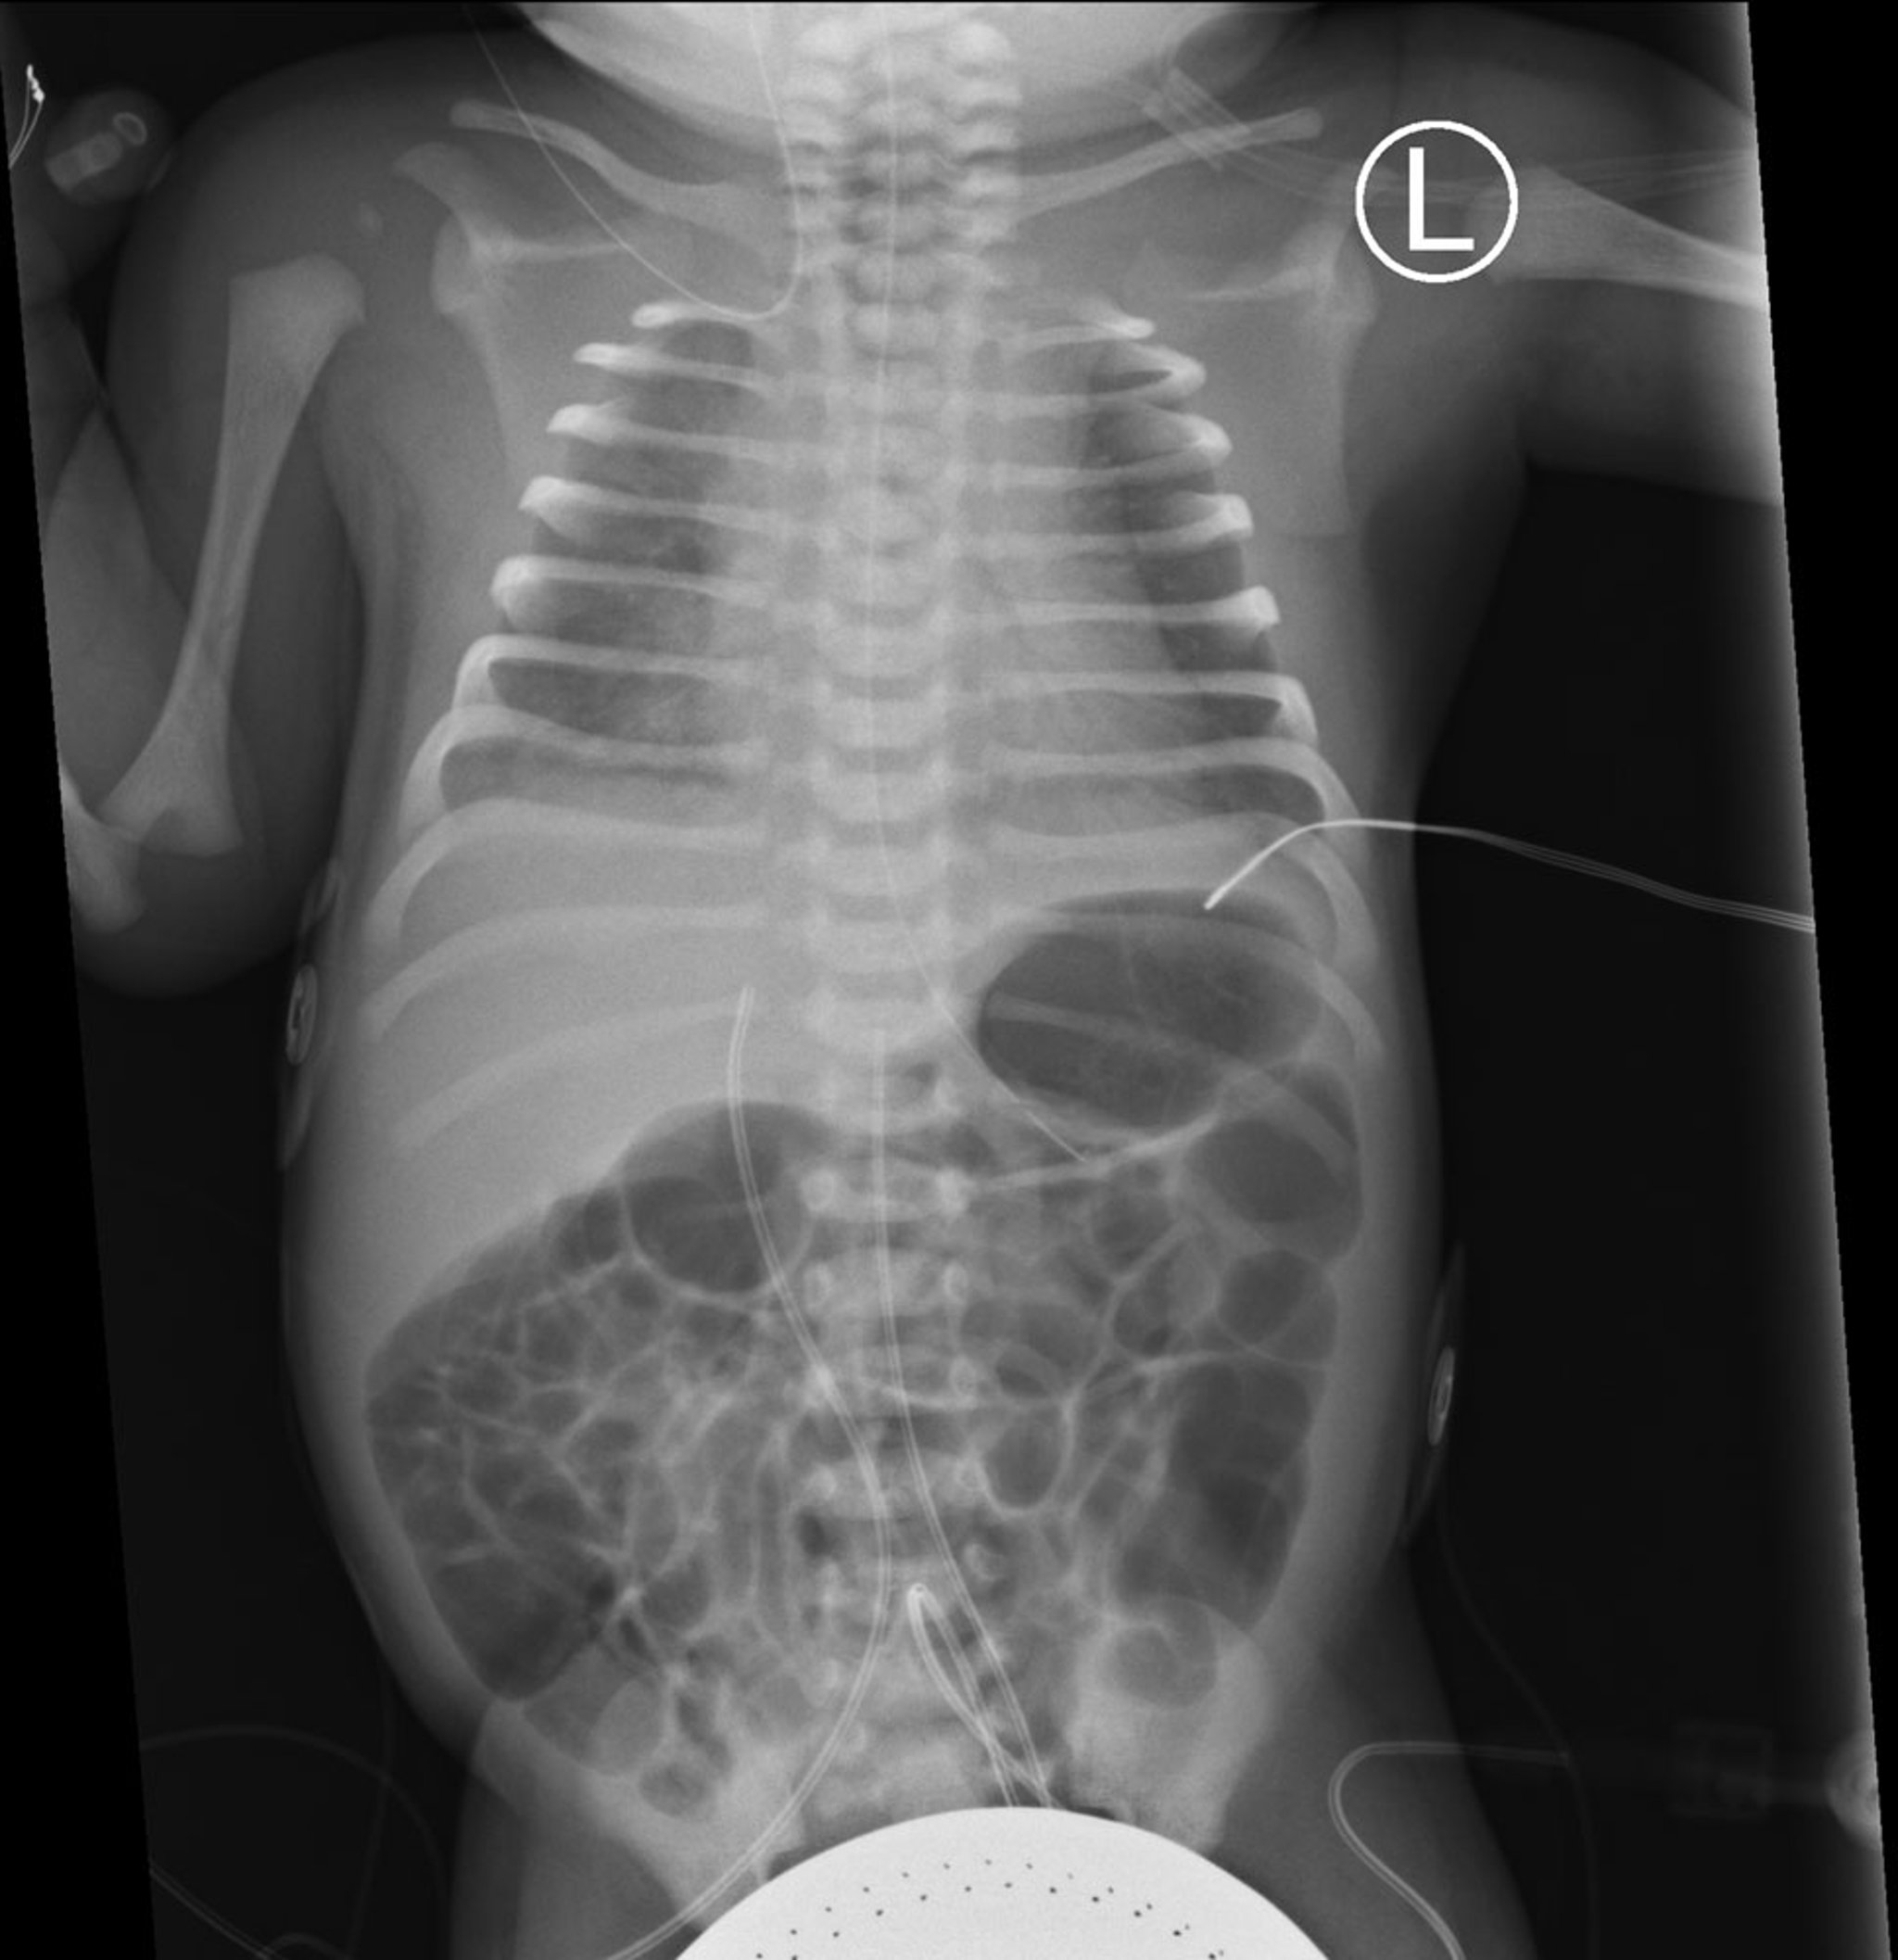

胸腹平片正位显示双肺弥漫性磨玻璃影伴支气管充气征,符合呼吸窘迫综合征(RDS)。

在预期位置也可以看到胃管以及脐动脉和静脉导管。